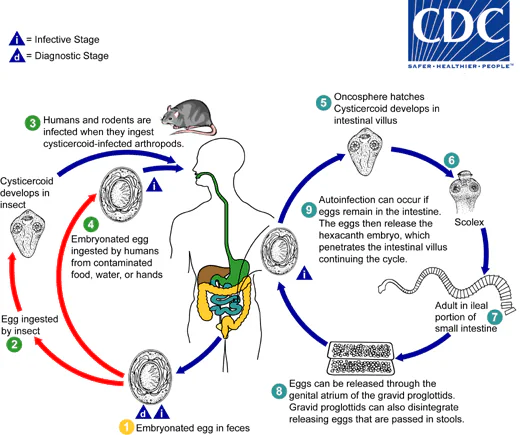

Life Cycles

Hymenolepis nana

Eggs of Hymenolepis nana are immediately infective when passed with the stool and cannot survive more than 10 days in the external environment  . When eggs are ingested by an arthropod intermediate host

. When eggs are ingested by an arthropod intermediate host  (various species of beetles and fleas may serve as intermediate hosts), they develop into cysticercoids, which can infect humans or rodents upon ingestion

(various species of beetles and fleas may serve as intermediate hosts), they develop into cysticercoids, which can infect humans or rodents upon ingestion  and develop into adults in the small intestine. A morphologically identical variant, H. nana var. fraterna, infects rodents and uses arthropods as intermediate hosts. When eggs are ingested

and develop into adults in the small intestine. A morphologically identical variant, H. nana var. fraterna, infects rodents and uses arthropods as intermediate hosts. When eggs are ingested  (in contaminated food or water or from hands contaminated with feces), the oncospheres contained in the eggs are released. The oncospheres (hexacanth larvae) penetrate the intestinal villus and develop into cysticercoid larvae

(in contaminated food or water or from hands contaminated with feces), the oncospheres contained in the eggs are released. The oncospheres (hexacanth larvae) penetrate the intestinal villus and develop into cysticercoid larvae  . Upon rupture of the villus, the cysticercoids return to the intestinal lumen, evaginate their scoleces

. Upon rupture of the villus, the cysticercoids return to the intestinal lumen, evaginate their scoleces  , attach to the intestinal mucosa and develop into adults that reside in the ileal portion of the small intestine producing gravid proglottids

, attach to the intestinal mucosa and develop into adults that reside in the ileal portion of the small intestine producing gravid proglottids  . Eggs are passed in the stool when released from proglottids through its genital atrium or when proglottids disintegrate in the small intestine

. Eggs are passed in the stool when released from proglottids through its genital atrium or when proglottids disintegrate in the small intestine  . An alternate mode of infection consists of internal autoinfection, where the eggs release their hexacanth embryo, which penetrates the villus continuing the infective cycle without passage through the external environment

. An alternate mode of infection consists of internal autoinfection, where the eggs release their hexacanth embryo, which penetrates the villus continuing the infective cycle without passage through the external environment  . The life span of adult worms is 4 to 6 weeks, but internal autoinfection allows the infection to persist for years.

. The life span of adult worms is 4 to 6 weeks, but internal autoinfection allows the infection to persist for years.

Hymenolepis diminuta

Eggs of Hymenolepis diminuta are passed out in the feces of the infected definitive host (rodents, man)  . The mature eggs are ingested by an intermediate host (various arthropod adults or larvae)

. The mature eggs are ingested by an intermediate host (various arthropod adults or larvae)  , and oncospheres are released from the eggs and penetrate the intestinal wall of the host

, and oncospheres are released from the eggs and penetrate the intestinal wall of the host  , which develop into cysticercoid larvae. Species from the genus Tribolium are common intermediate hosts for H. diminuta. The cysticercoid larvae persist through the arthropod’s morphogenesis to adulthood. H. diminuta infection is acquired by the mammalian host after ingestion of an intermediate host carrying the cysticercoid larvae

, which develop into cysticercoid larvae. Species from the genus Tribolium are common intermediate hosts for H. diminuta. The cysticercoid larvae persist through the arthropod’s morphogenesis to adulthood. H. diminuta infection is acquired by the mammalian host after ingestion of an intermediate host carrying the cysticercoid larvae  . Humans can be accidentally infected through the ingestion of insects in precooked cereals, or other food items, and directly from the environment (e.g., oral exploration of the environment by children). After ingestion, the tissue of the infected arthropod is digested releasing the cysticercoid larvae in the stomach and small intestine. Eversion of the scoleces

. Humans can be accidentally infected through the ingestion of insects in precooked cereals, or other food items, and directly from the environment (e.g., oral exploration of the environment by children). After ingestion, the tissue of the infected arthropod is digested releasing the cysticercoid larvae in the stomach and small intestine. Eversion of the scoleces  occurs shortly after the cysticercoid larvae are released. Using the four suckers on the scolex, the parasite attaches to the small intestine wall. Maturation of the parasites occurs within 20 days and the adult worms can reach an average of 30 cm in length

occurs shortly after the cysticercoid larvae are released. Using the four suckers on the scolex, the parasite attaches to the small intestine wall. Maturation of the parasites occurs within 20 days and the adult worms can reach an average of 30 cm in length  . Eggs are released in the small intestine from gravid proglottids

. Eggs are released in the small intestine from gravid proglottids  that disintegrate after breaking off from the adult worms. The eggs are expelled to the environment in the mammalian host’s feces

that disintegrate after breaking off from the adult worms. The eggs are expelled to the environment in the mammalian host’s feces  .